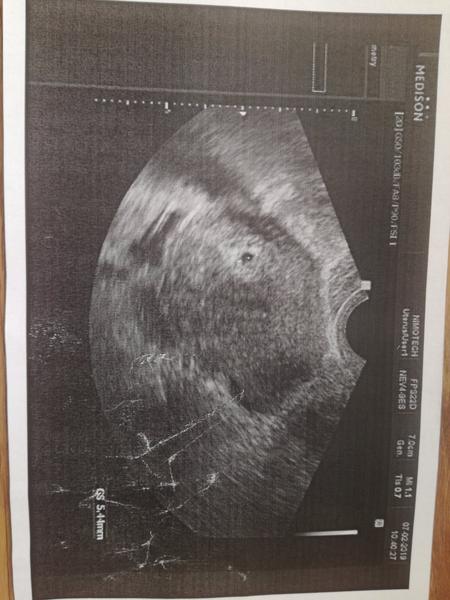

Vidite tam ducha?

Na fotce je tu hůř vidět

Tak mě radost trošku přešla 😐 čárka neni silnější, je stejně silná (slabá jak vcera)...

@vladivojna tak jak to vypadá? 🙂

@karoczde dnes